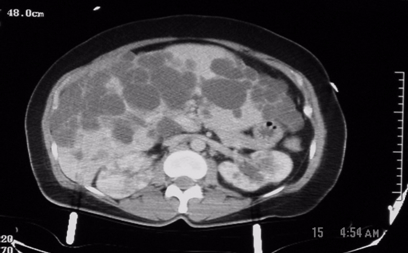

Figure1: These are two contiguous computerized axial tomographic sections of the abdomen obtained after intravenous infusion of contrast.They show an enlarged liver that contains multiple cysts ranging in size from a few to several centimeters, diffusely spread throughout the organ. The kidneys also contain several (>5 total, bilaterally) similar though much smaller cysts but they are not very large. The pancreas, at least to the naked eye, is spared. There are no other obvious abnormalities; the lady, fortunately, had no significant intra-abdominal injuries from her trauma.

Radiologic diagnosis: Autosomal Dominant Polycystic Disease (ADPD).